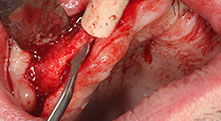

Piezomed B6

La cresta alveolare è stata incisa su entrambi i lati tramite piezochirurgia (strumento utilizzato: Piezomed B6). Gli impianti sono stati posizionati con la stessa procedura e l'osso peri-implantare è stato costruito con la tecnica GBR.